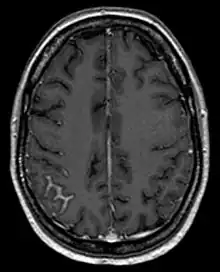

L'analyse des cellules dans le liquide cérébrospinal lors d'une ponction lombaire peut faire le diagnostic mais nécessite parfois d'être répétée[3], l'absence de cellules suspectes se voyant dans un quart des cas[4]. L'IRM cérébrale peut également aider[5].